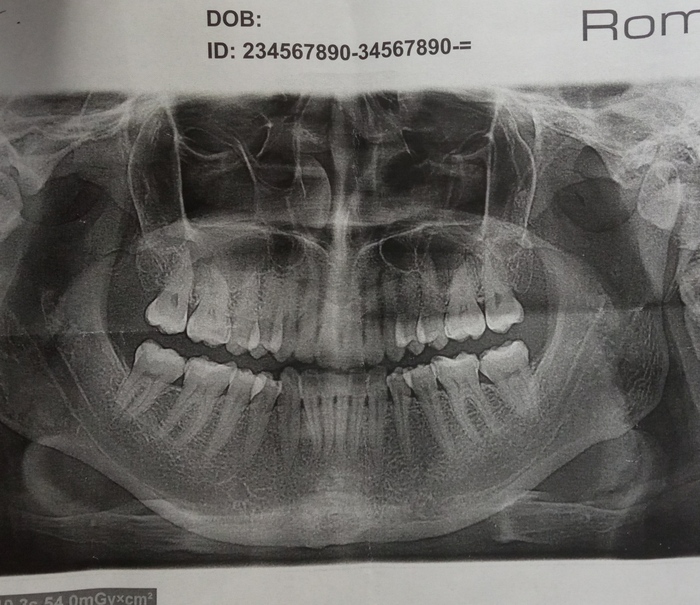

Пришла, врач говорит, мол, я так ничего не вижу, ничего не опухло, но можем сделать панорамный рентген чтоб лучше увидеть. Я согласилась (это поликлиника обычная). Рентген сделали и я даже видела как мои зубы отображаются на экране.

И она говорит.... А у вас зубов мудрости нет даже в зачатках. Всё хорошо, ни воспалений, ни кариеса (ни зубов).... Проблема скорее всего с суставом и это к терапевту.